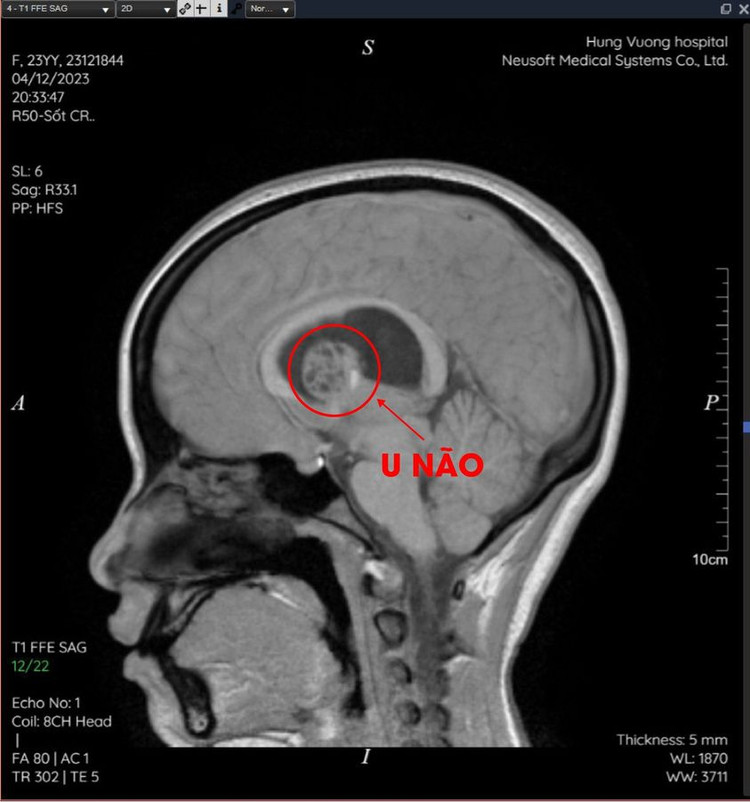

Sau khi được chụp cộng hưởng từ và tiến hành hội chẩn với ý kiến các chuyên gia đầu ngành, các bác sĩ tại Khoa Chẩn đoán hình ảnh - BVĐK Hùng Vương kết luận: U đám rối mạch mạc não thất bên bên phải xâm lấn hồi hải mã phải.

| Khối u não trên phim chụp |